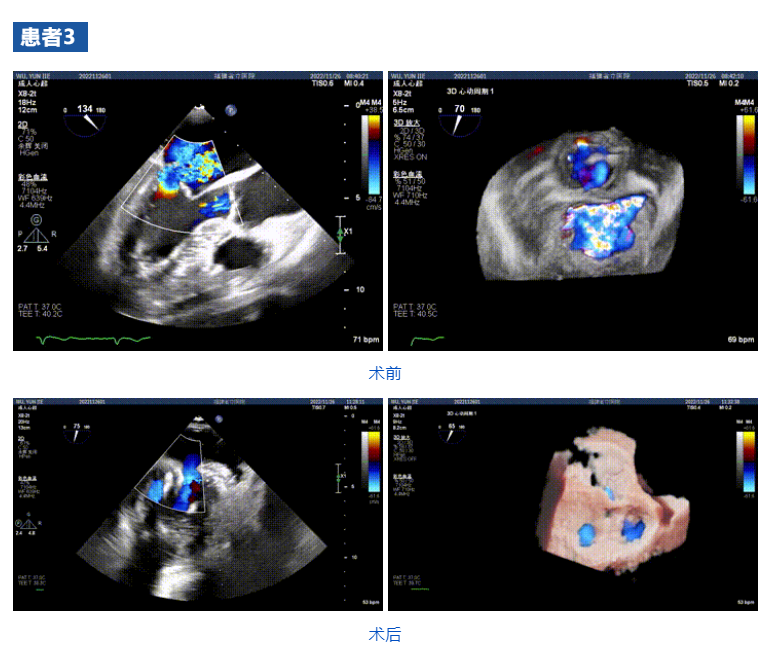

接受治療的三例患者均為器質(zhì)性重度二尖瓣反流(DMR)患者,術(shù)前超聲提示二尖瓣后葉脫垂伴4+反流,左室舒張功能減退。郭延松教授攜同團(tuán)隊(duì)成員陳新敬副教授和洪景宣、方明程、楊清勇主治醫(yī)師、心外科丁杭主任以及超聲科賴寶春、葉振盛主治醫(yī)師共同進(jìn)行病情討論??紤]到患者高齡、基礎(chǔ)疾病多、STS評(píng)分高,為外科手術(shù)極高危患者,不適合進(jìn)行外科開胸二尖瓣手術(shù),因此決定為患者實(shí)施經(jīng)導(dǎo)管緣對(duì)緣修復(fù)介入術(shù)(JensClip經(jīng)導(dǎo)管瓣膜夾系統(tǒng))。

在浙江大學(xué)醫(yī)學(xué)院附屬第二醫(yī)院王建安教授團(tuán)隊(duì)的支持下,手術(shù)經(jīng)股靜脈-房間隔入路,采用全身麻醉插管,在TEE和DSA引導(dǎo)下完成房間隔穿刺。置入JensClip瓣膜夾系統(tǒng)后,在左房調(diào)整瓣膜夾的位置和軸向,后進(jìn)入左室,在TEE引導(dǎo)下捕捉二尖瓣前后瓣葉,并關(guān)閉瓣膜夾。經(jīng)TEE反復(fù)確認(rèn)手術(shù)效果后最終鎖定并釋放瓣膜夾。術(shù)后即刻超聲顯示瓣膜夾位置穩(wěn)定,功能良好,二尖瓣反流由術(shù)前4+減少至微量,手術(shù)圓滿成功。